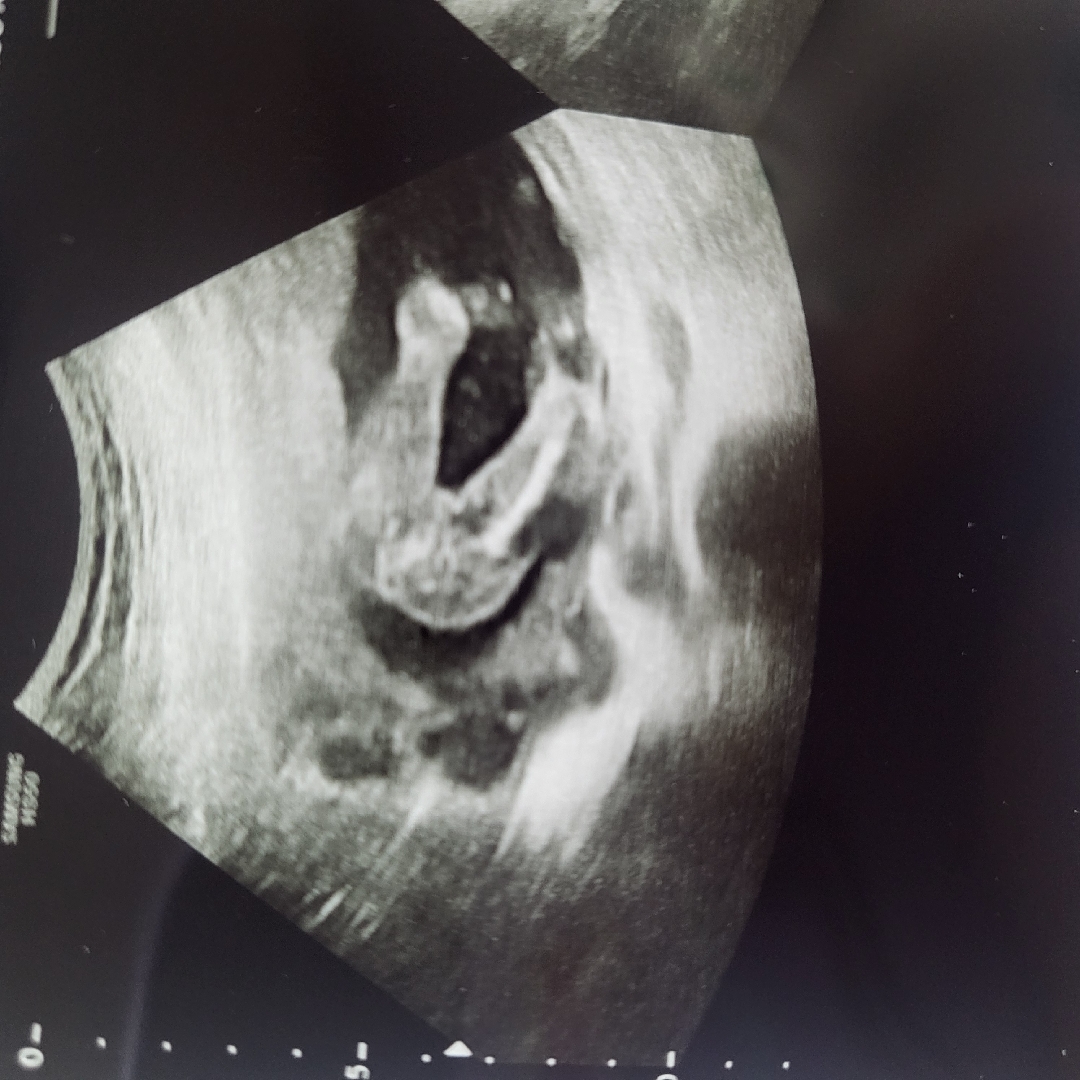

17주차 성별보고왔어요~

선생님께서 80% 딸인거 같다고 말씀해주셨는데ㅎㅎ 어떻게 생각하시나요?ㅎㅎ 80% 라고 하셔서... 바뀔수도 있나요?

17주차면 딸 확정인듯요 매끈하네요

남자아기는 17주차정도면 자기주장 확실하더라구요! 여자아기 맞아보여요🙂🙂